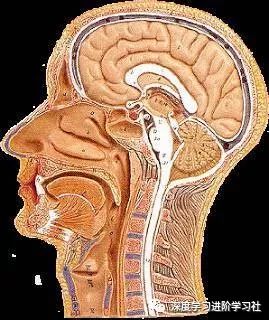

我们从外往里看吧。生物学有时似乎非常让人满意,比如你的头上有一个真正的俄罗斯套娃。

你有头发,然后是头皮,你认为下面就是你的头骨了——但实际上头骨之上还有19样东西。

你的头骨下面,又是一大堆东西,之后才是你的大脑:

在你的头骨下面,大脑周围有三个膜,将大脑环绕:

在外面,有硬脑膜,坚固耐用,防水。硬脑膜与颅骨齐平。我听到有人说,大脑中没有疼痛感觉区,但硬脑膜实际上能感觉疼痛,且和你的面部肌肤一样敏感,硬膜上的压力或挫伤往往造成了人们严重的头痛。

然后下面是蛛网膜,这是一层皮肤,然后是带有弹性的纤维的开放空间。我一直以为我的大脑只是漫无目的地漂在我大脑中的某种液体里,但实际上,脑外和颅骨内壁之间的唯一真正的空间差距是这个蛛网膜。这些纤维稳定了大脑的位置,因此不能动作太大,他们充当减震器,当你的头撞到东西。这个区域充满了脊髓液。

最后,是软脑膜,和脑外融合的很精巧的皮肤层。你知道,当你看到一个大脑,它总是覆盖着恶心的血管。但这些并不是真正在大脑的表面上,它们埋设在里面。

下面是完整的样子,使用的样品可能是猪的大脑:

从左到右是皮肤(粉红色),然后是两个头皮层,然后是头骨,然后是硬脑膜,蛛网膜,最右边是只由软脑膜覆盖的大脑。